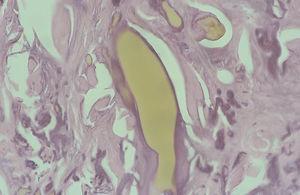

Se tomó, una biopsia de la cara lateral de uno de los índices afectados, y se observó una epidermis discretamente hiperqueratósica y acantósica. En la dermis superficial había una importante elastosis asociada a depósitos de material acelular de color ocre rodeado de una degeneración basófila del colágeno (figs. 3 y 4).

Fig. 3.--Fibras de colágeno irregulares con bordes dentados y fracturadas en relación con cúmulos alargados de pigmento ocre de tamaño grande y pequeño. Algunos en íntima relación con la dermis papilar y epidermis con aspecto de estar en situación previa a su eliminación transepidérmica. (Hematoxilina-eosina, x100.)

Fig. 4.--Detalle de cúmulos de pigmento de diverso tamaño, el más grande con la forma alargada típica y otras de menor tamaño en íntima relación con las fibras de colágeno de aspecto degenerativo elastótico. (Hematoxilina-eosina, x400.)

En estudios microscópicos de la piel, el pigmento forma depósitos dérmicos, de color pardo-amarillento, redondeados y alargados en forma de plátano y en estrecha relación con masas de colágeno degenerado. En el caso de la biopsia de nuestro paciente se apreciaron claramente los hallazgos más característicos de esta enfermedad: fibras de colágeno irregulares con bordes dentados y fracturadas en relación con cúmulos redondeados y alargados de pigmento amarillento de diversos tamaños. Sin embargo, no se observaron macrófagos cargados de pigmento en el interior de células endoteliales en células secretoras, ni en la membrana basal de glándulas sudoríparas, hecho descrito también en algunos casos de alcaptonuria. Asimismo se apreciaban grandes depósitos en dermis papilar, lo que indica una probable tendencia a la eliminación transepidérmica en nuestro caso, tal y como se ha descrito en casos de ocronosis exógena 7. Sin embargo, en esta última las fibras ocres son de pequeño tamaño, están dispuestas de forma dispersa en toda la dermis y no se describe la presencia de grandes fibras ocres en la dermis superior. Al igual que en la forma endógena, también se aprecian pequeños gránulos de pigmento ocronótico en el interior de macrófagos. En los casos inducidos por hidroquinona los macrófagos cargados de pigmento están situados en la dermis superior y habitualmente asociados a escasa melanina en la capa basal epidérmica. En los casos inducidos por antipalúdicos estos macrófagos se sitúan a nivel perivascular y perianexial 7. La determinación de AHG en orina se considera patognomónica de esta enfermedad (valores normales en orina: < 0,01 mmol de AHG por mol de creatinina o < 10,0 mg en orina de 24 h) 8.